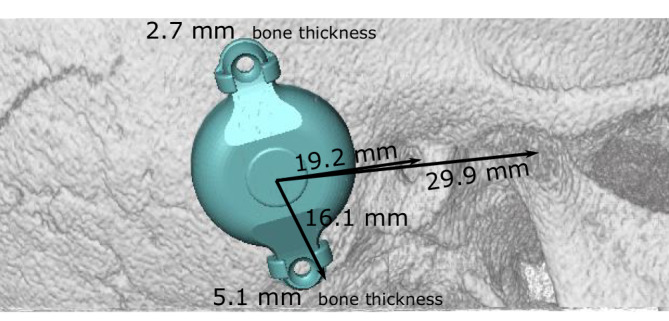

Further development of the BCI 601 (the BCI 602) reduced the penetration depth of the BC-FMT from 8.7 to 4.5 mm. This was achieved by increasing the BC-FMT diameter from 15.8 to 18.2 mm and locating some components of the BC-FMT above the bony surface. With the additional use of 1‑mm spacing washers (BCI 602 Lifts), the implantation depth can be further reduced to 3.5 mm. This configuration elevates the BC-FMT to 5.1 mm above the bony surface. The anchor holes in the fixation wings are 24.4 mm apart (BCI 601: 23.8 mm; Fig. 1).

Fig. 1.

Comparison of the bone conduction implants (BCI) 601 and 602. Images show the new active bone conduction hearing system, BCI 602 (right), and the previous model, BCI 601 (left), (© MED-EL, Innsbruck, Austria, with permission). Virtual three-dimensional (3D) models of the bone conduction-floating mass transducers (BC-FMT) are used for preoperative planning. All measurements are expressed in millimeters

The implantable component of the bone conduction implant BCI 602 consists of an FMT with the electronics and an attachment magnet surrounded by the receiver coil (Fig. 1). The external part, the audio processor, is held in place by the magnet.

With the new active BCI and its optimized geometry, the anatomical indication range has significantly increased compared to the previous model (BCI 601). A study that performed “virtual surgery” in 151 temporal bones of 81 children and young adults (ages 5 months–20 years) demonstrated that, in all patients aged 12 years and older, the BCI 602 could be completely fitted to the bone. In patients aged 3–5 years, the BCI 602 could be fitted to the bone in 75% of cases. In contrast, a complete bone fit was not achieved with the BCI 601 in any of the temporal bones without BCI lifts [33]. However, the BCI 602 has not been approved for this age group of up to 5 years. A lower penetration depth would entail a reduced volume of the BC-FMT. However, adequate acceleration of the skull, which is necessary for stimulating the inner ear, would be difficult to achieve. The resonance frequency is indirectly, exponentially related to the mass of the BC-FMT (~m−1/2). Thus, for an electromagnetic transducer with a given mass and resonance frequency, a lower penetration depth required a larger diameter (BCI 601: 15.8 mm and BCI 602: 18.2 mm; Fig. 1). This corresponds to a 15% increase in the diameter and a 45% reduction in the volume of the implant bed. The latter was reached by partially translocating the BC-FMT above the skull surface (Fig. 1). Due to the translocation of the electronics (demodulator) into the BC-FMT, the overall “footprint” of the implant has decreased. Consequently, depending on the individual configuration of the temporal bone, implantation in children under 5 years old appears to be possible and has been performed (off-label) in individual cases (Fig. 10).